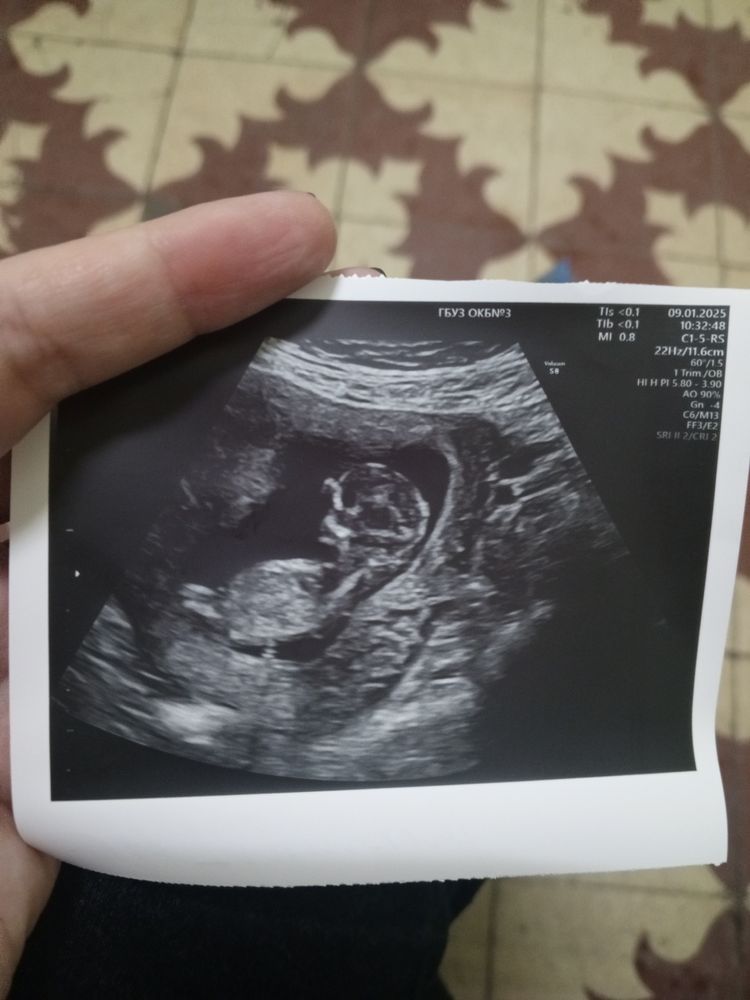

Пол ребёнка 👨‍👩‍👧‍👦

Никак по фото УЗИ не определить пол. Если врач вам не сказал значит не видно. Можно по методу Елены Феликсены высчитать пол по датам. Мы у нее делали планирование пола до зачатия всё получилось. Но самое надёжное это кровь сдать на хромосомы. А по фото гадать это так же что и на ромашке.

Тут нет ничего, чтобы указывало на пол, кроме ног.

У врача узиста надо было спросить, по фото вообще не понятно, ну или ждать 2 скрининг. Мы на фото не гадали просто спросили видно или нет, сказали 90%, в 16 подтвердили.